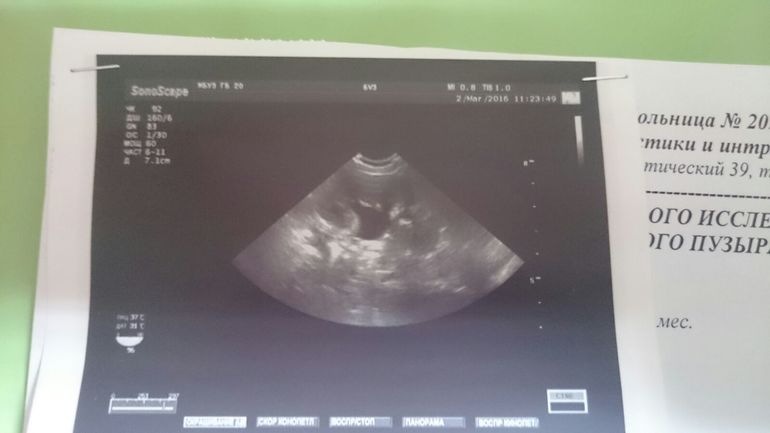

Добрый вечер Максим Викторович! Мы с сыном сейчас лежим в больнице (г.Ростов -на-дону. Урология #20, в нефрологическом отделении). Сами мы из г. Волгограда. Родился 25.11.2015. Но уже 3 января у малыша была температура 38,5..Орви врачь исключил...т.к.были праздники пришлось вызвать платного врача на дом. Сказали, что может из за стула(а он у нас был жидким..т.к.в роддоме после кесарево сечения кололи антибиотики)... Связи с переездом полное обследование после месяца пришлось отложить... В две месяца на УЗИ нам сказали,что у левой почки увеличены лаханка 1,1см чашечки 0,6 см..ОАМ был в норме.Педиатр назначил элькар...Но у малыша повысился аппетит и появился ужасный запах мочи..После чего ппереслали малышу элькар давать.. 19 февраля повторно сдавали анализы. Все показания были в пределах нормы... Но 28 февраля у малыша заметила изменения цвета мочи и прожилки крови..при этом повысилась температура... При поступлении в больницу в оам на все поле зрение лейкоциты и обнаружили кровь..Но следующий повторно сдали ОАМ. Кровь в моче не обнаружили, но лейкоциты на все поле зрение. На данный момент малышу поставили диагноз острый пиелонефрит,колят антибиотики 3 р в день.. Сделали 2 марта повторно УЗИ. Первая почка в норме, а у левой расширеная лоханка и чашечки... Врачь советует сделать рентгеноурографию...